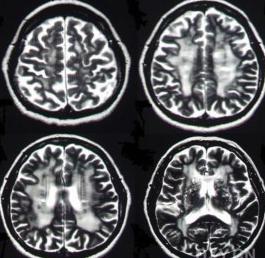

3.體徵可有原始的吸吮反射,抓握反射和伸性肌強直等。部分病例CT或MRI可顯示胼胝體變窄和局限性萎縮。

本病診斷非常困難,如嚴重的慢性酒精中毒患者出現上述臨床表現,應懷疑本病。但死前很少明確診斷。通常是死後屍體解剖確診。少數病例CT或MRI能顯示胼胝體病變。

胼胝體變性患者胼胝體密度減低,呈均勻或部分欠均勻的低密度影;無占位性徵象,有腦萎縮表現,其中有廣泛性腦白質病變。胼胝體發生腦梗塞少見,梗塞多為小腔隙性梗塞灶,不會出現與胼低體形態相同的低密度影,腫瘤為占位性病變,有占位徵象。患者的CT表現為胼胝體密度均勻性或部分均勻性減低,CT值均在20HU以下,正常中老年人胼胝體CT值均在23HU以上,具有特徵性,急性期增強可有強化,晚期不強化,診斷不難胼胝體變性,多認為與酒精中毒有關。胼胝體變性臨床表現缺乏特異性,因而診斷困難,以往報導病例多為屍解發現,隨著影像診斷學發展,其早期診斷成為可能。

胼胝體進行性變性治療MRI是診斷胼胝體變性最有價值的診斷方法。MRI與CT比較,有多角度、多序列成像優勢,特別是矢狀位、冠狀位比CT顯示病變更早、更準確、更全面,較易與其它疾病鑑別。FLAIR序列能抑制腦脊液的高信號,使病變顯示更加突出,並可區別病灶的新舊程度,進展期表現為高信號,軟化灶形成後為低信號,還可顯示腦萎縮情況及與胼胝體變性並存的其它部位白質脫髓鞘情況,顯示病灶為高信號,說明病灶為進展期,為臨床治療提供可靠依據。一般認為胼胝體變性異常強化持續不超過20天,發病3周后將不出現強化。有研究提示急性發病的胼胝體變性多累及膝部和壓部,慢性表現的病例體部受累多見。